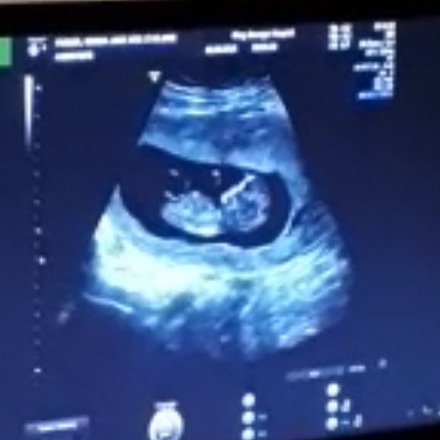

Baby blue nub?

I Have been guessing nubs for quite a few years now, it never have I ever come across a nub that looks so blue so early! I've asked some of my nub friends and that have said that they cannot see this baby being a baby girl in any way, even at the gestation 11+4 (12+4 by dates). What do you all think? I've only seen longer flatter nubs at this gestation, with time to change to a boy,never one so risen. I thought what goes up doesn't come down! XxAttachment 40075

I'm not sure that that is the nub.

BUT the way nubs work is that all babies start off looking girly, and then around 10 weeks baby boys' Y chromosomes "wake up" and start making testosterone and then under the influence of testosterone, the "girly" parts start to look "boyly". This can happen for some babies faster than others so if a baby is a clear boy in the 11th week, that ~generally~ means that it is a boy. But a baby that still looks girly may still be a boy, just isn't obvious yet.

Soooo, long story short, it could possibly be a boy (because just liek u say, what goes up, doesn't come down) BUT sometimes things are captured that look like boy parts but are actually something else entirely and I wonder if we may be looking at one of those situations. 50-50 from me. :)